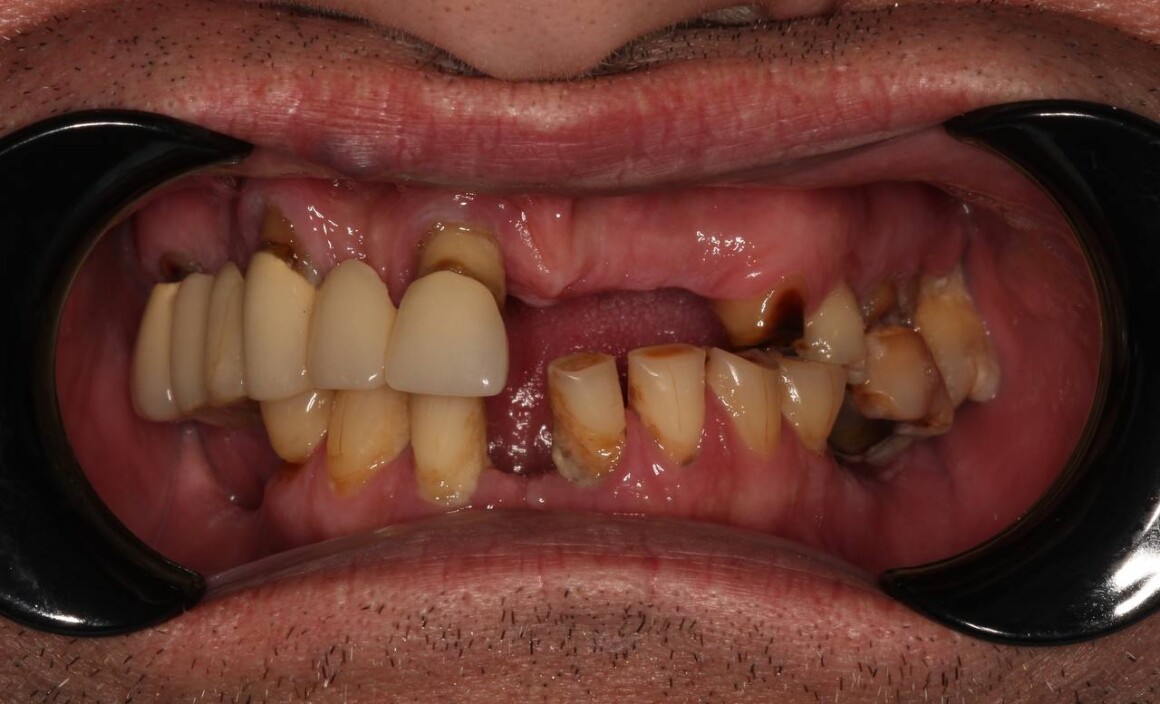

Постоянный протез ALL on 6 на верхней челюсти

Имплантация ALL on 4 на верхней и нижней челюстях в день операции